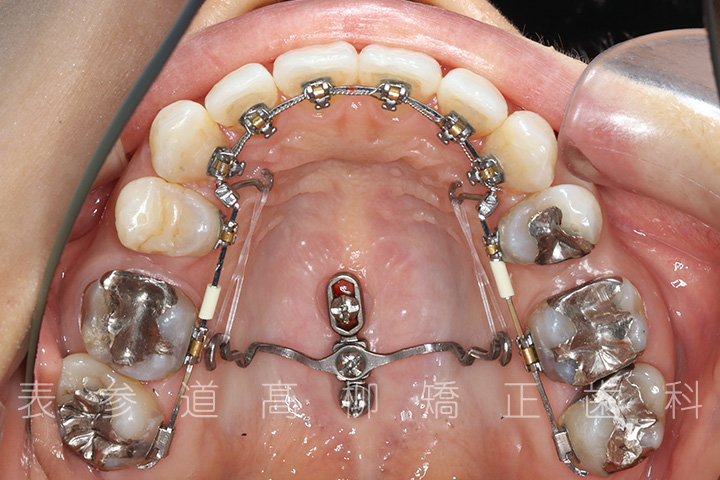

・上下両側第二小臼歯を抜歯

・マウスピース型矯正装置と歯科矯正用アンカースクリューを併用し、上顎臼歯部を圧下

・歯科矯正用アンカースクリュー(i-station)を併用し、前歯部を後方へ移動する

・歯科矯正用アンカースクリューを併用し、下顎大臼歯の近心移動(前方への移動)

・上下歯列の緊密な咬合関係の確立に顎間ゴムを併用(装着時間20時間以上/日)

・マウスピース型矯正装置よる嚙み合わせの微調整

治療に用いた主な装置

・リンガルブラケット装置

・歯科矯正用アンカースクリュー(i-station)

・マウスピース型矯正装置